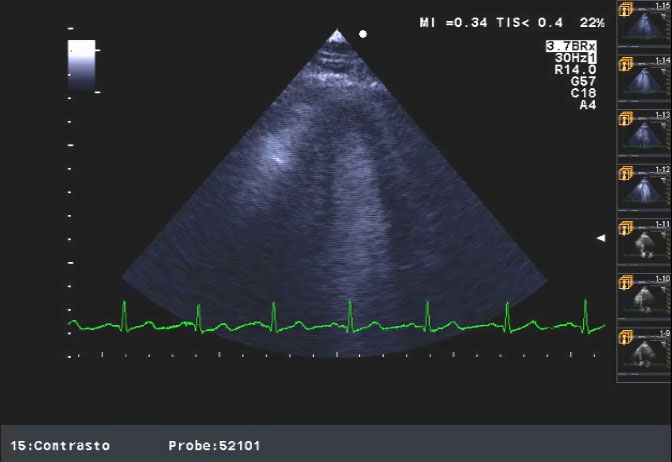

La diagnosi con Eco2DColorDoppler di stenosi valvolare aortica e la low flow low gradientAutore: Laura Massironi